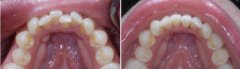

儿童牙齿拥挤问题严重吗?

经常接到类似的咨询,说孩子前牙比较不齐,应该属于拥挤那一类的,请问这种...【详细】